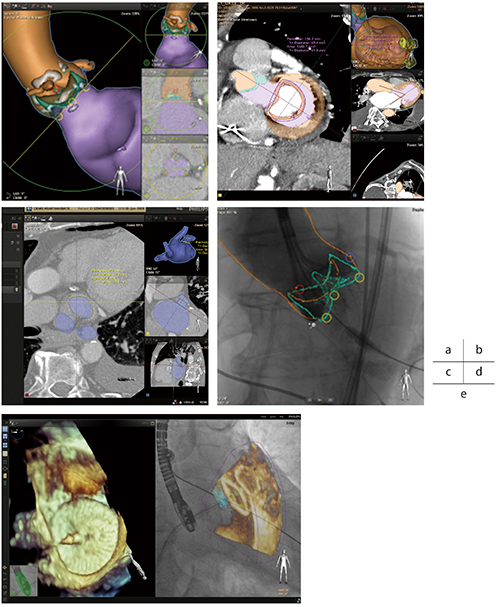

術前のCT画像によるプランニング,術中のX線透視画像とオーバーレイした3Dロードマップが可能である。術前CT画像は自動でセグメンテーションされ,以下の各手技に合わせた最適観察のアングルが自動で表示される。また,術者の最適なアングルを追加,保存することもできる(図4 a〜c)。

最適なアングルのCT画像を2方向の撮影情報からレジストレーションし,X線透視とオーバーレイした3Dロードマップによりプランニングに沿った手技を支援できる(図4 d)。

2.Echo Navigator

SHDインターベンションでは,血管撮影システムに加え,3D経食道心エコー(以下,TEE)も必要不可欠である。Echo Navigatorは,X線透視画像とLive TEE画像を“Smart Fusion”機能により融合することを可能とした(図4 e)。Smart Fusion機能では,X線透視画像上に表示されているTEEのプローブの形状を特定し,X線透視画像とLive TEE画像の位置情報を自動で認識し,フュージョンさせることができる。

最大3つの異なる2Dまたは3D TEE画像を大型モニタ上に自由なレイアウトで同時に表示し,組織構造とデバイスの位置情報を明瞭に把握できる。

フュージョンされた画像は,Cアームの動きとリアルタイムに連動して表示される。

FlexArmでは,斜め方向からの設置でも連動でき,柔軟なポジショニングに対応しており,術者,スタッフの操作スペースも十分に確保できる。また,TEE画像上で組織構造上に設定されたマーカーは,自動的にリアルタイムX線透視画像上に表示され,安全かつ適切なデバイスのポジショニングが可能となる。

図4 SHD Suite

a:Heart Navigator・TAVIプランニング

b:Heart Navigator・Mitral valve replacementプランニング

c:Heart Navigator・LAAC procedure プランニング

d:Heart Navigator・3Dロードマップ

e:Echo Navigator・Smart Fusion機能